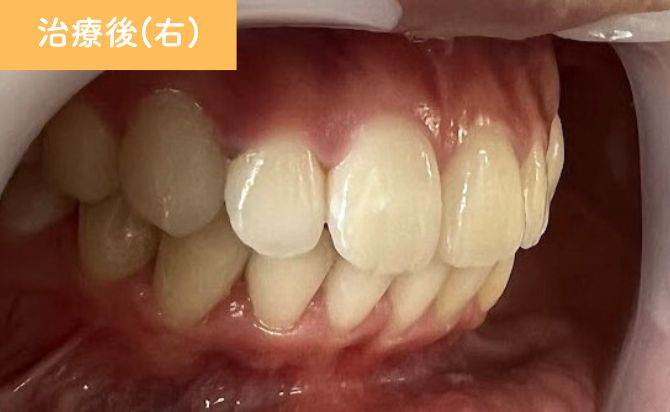

歯並びの変化(右)

治療終了時には、上顎前歯の前突が改善し、

唇元の突出感が軽減したことで横顔のバランスも向上しました。

歯列全体のアーチも整い、前歯の噛み合わせが適切な位置に改善。見た目だけでなく、機能的にも安定した咬合が得られています。